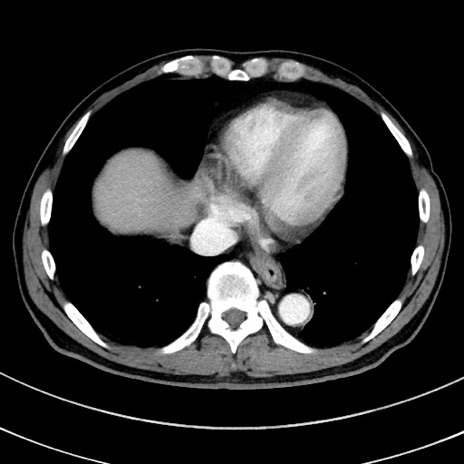

冠状断像

症例8(横断像)

【症例】 60歳代男性

【主訴】 黒色吐物

【現病歴】 4日前から嘔気自覚、2日前の朝食後にも嘔気あり、自分で手で嘔吐反射起こし嘔吐したところ血が混ざっていたため受診。

【既往歴】 5年前汎発性腹膜炎を伴う急性虫垂炎で手術、高血圧、前立腺肥大症、高脂血症

【身体所見】 腹部正中に手術癩痕あり 腹部平坦・軟圧痛なし膨満感あり

【データ】WBC 8400、CRP 4.54